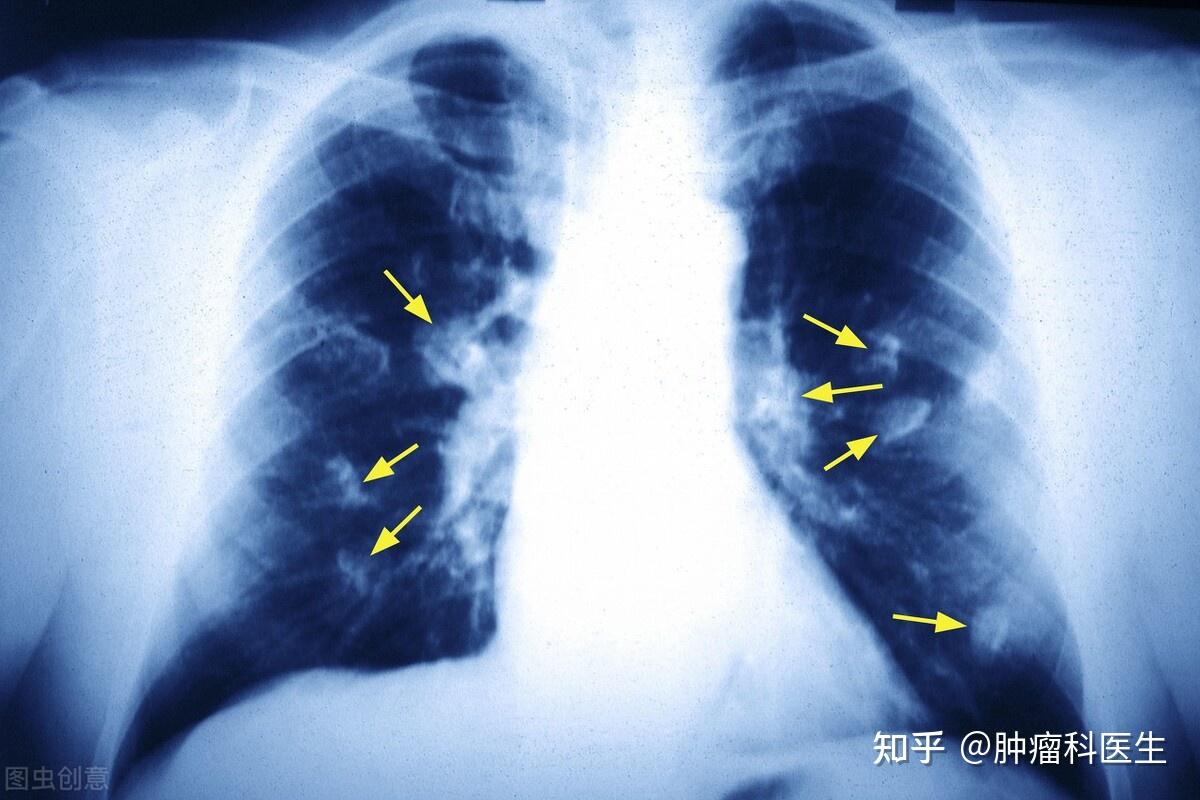

肺癌形成原理: 肺部组织的相关细胞受多种因素的影响,发生了 基因的突变 ,使得原本会"正常死亡"的细胞变得"永不死亡",且生长迅速,形成细胞团块,形成了肺癌。 肺癌分类从病发部位来分: 1、中央型肺癌(多为鳞癌和小细胞肺癌) 2、周围型肺癌(多为腺癌) 根据组织病理来分: 1、小细胞肺癌(占15%;男性易发与吸烟相关; 恶性最高 ;手术切除效果差对药物比较敏感) 2、非小细胞癌(占85%;鳞状细胞癌、腺癌、大细胞癌) 这是肺癌的大致分类,至于 肺癌的分期也要分小细胞癌和非小细胞肺癌来划分 。 小细胞癌分为 : 1、局限期(尚未转移到肺以外的部位) 2、广泛期(转移到肺周围或除了肺以外的其他部位) 非小细胞分为: I(早)、II(中)、III(中晚)、IV(晚)期,转移程度依次加深。